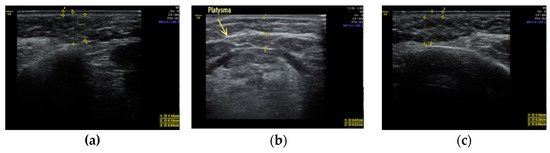

Clinical case #3. During the study, a 46-year-old female patient with a 24 MHz linear transducer of soft tissues of the lower third of the face and neck without pressure, in an upright position, exhibited the absence of the accumulation of adipose tissue along the contour of the lower jaw from two sides (Figure 3a,b) and sagging of a rather thin platysma (diameter 0.36 mm), causing age-related contour deformities (Figure 3c).

Figure 3.

B-mode ultrasound examination of the soft tissues of the lower face and submandibular area with a 24 MHz linear transducer. Absence of the accumulation of adipose tissue along the contour of the lower jaw from both sides (a,b), and sagging platysma causes age-related contour deformities (c).

Accordingly, it is correct to direct the efforts of a plastic surgeon to the correction of ptotic platysma in the presented clinical case, which will be sufficient to obtain a good clinical result.